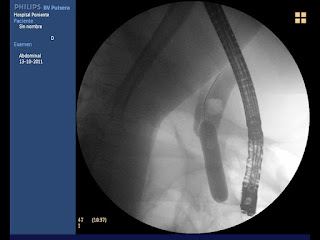

ENDOSCOPIA DIGESTIVA: Esfinteroplastia: es importante dilatar desplazando la litiasis por encima del balón (F. Gallardo)